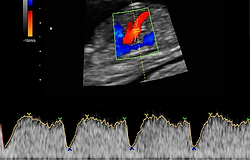

ECOGRAFÍA DOPPLER

¿Qué es la Ecografía Doppler?

La ecografía Doppler es un tipo de ecografía que nos permite valorar la circulación sanguínea fetal y materna mediante la visualización y medición del flujo sanguíneo de ciertas arterias y venas ampliamente conocidas. Además también es útil para valorar la circulación al útero.

Arteria Uterina

(Valoración Preeclmapsia)